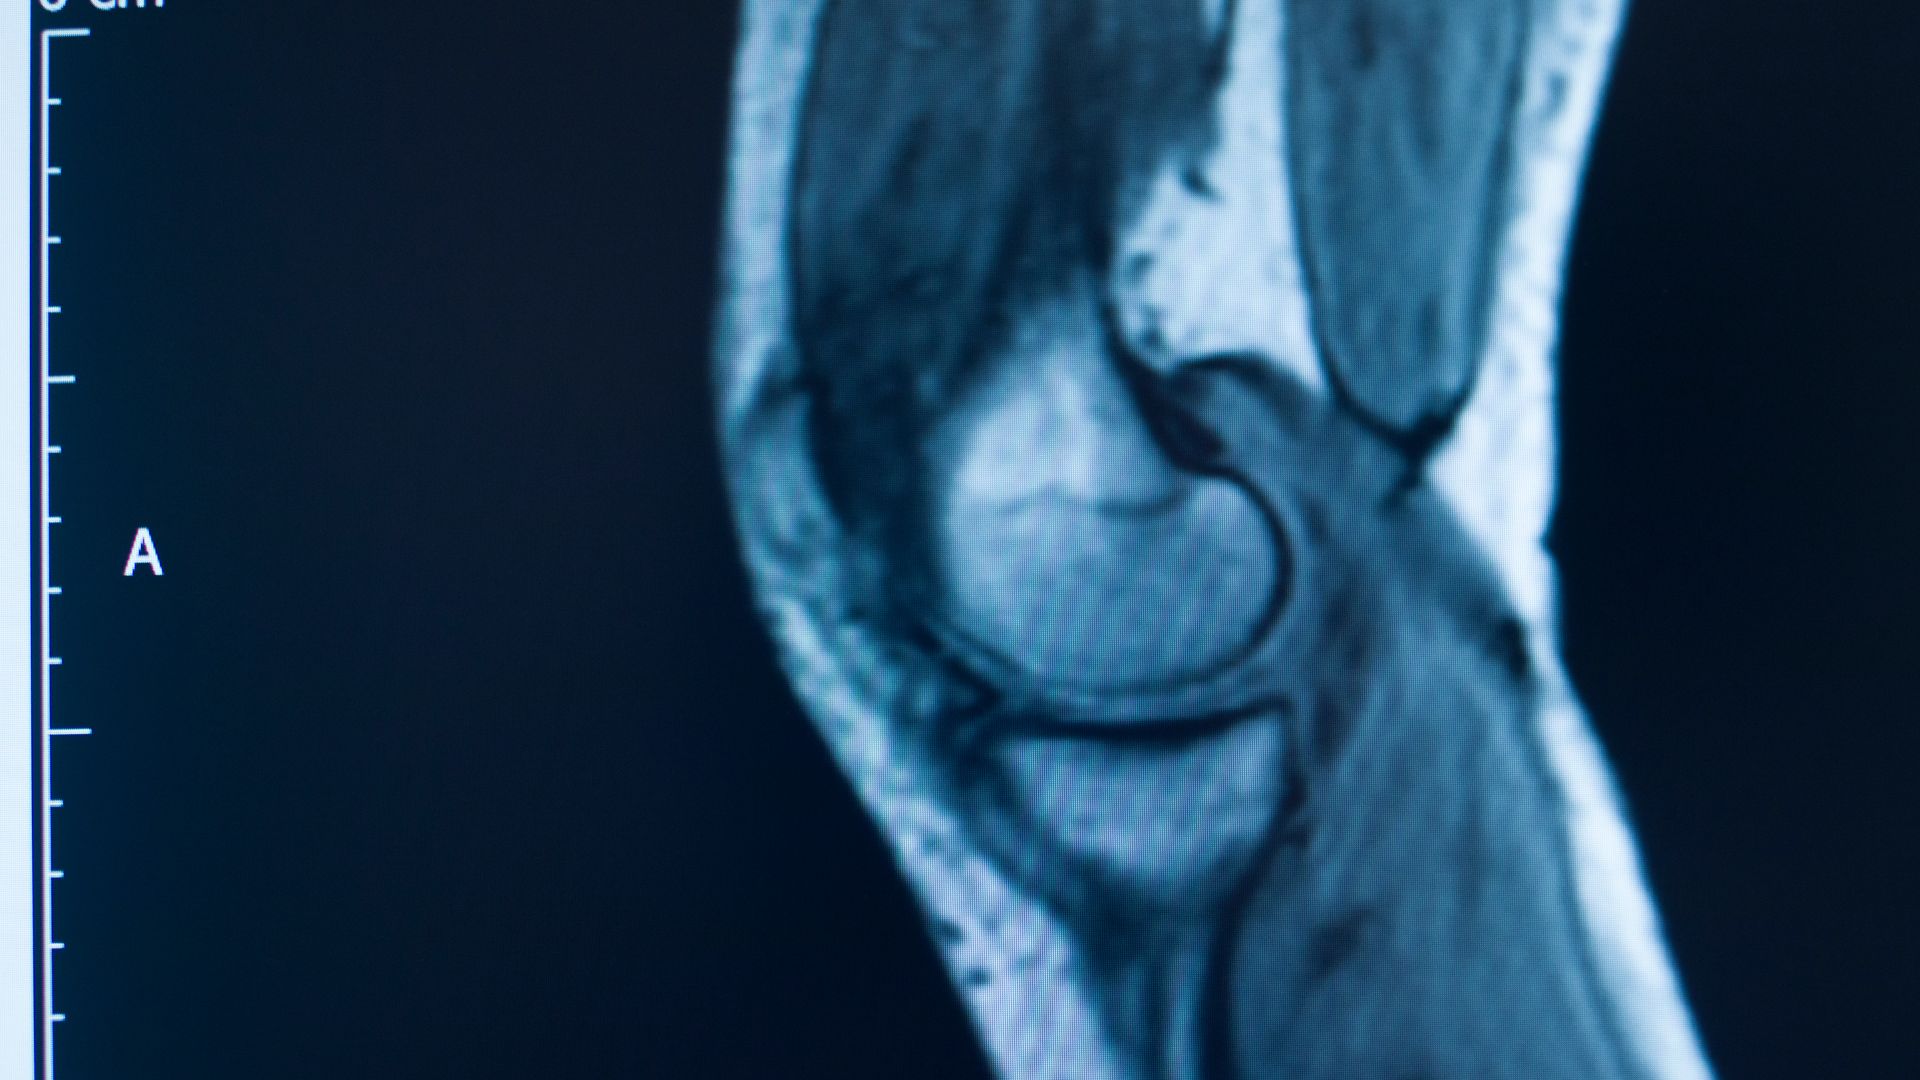

Despite the ongoing treatment, Jane’s knee became more unstable and further exploratory surgery carried out by the surgeon in question indicated that her ACL had ruptured. Within the records, the surgeon made it clear that it was his view that this had happened when she had slipped and fallen at work, despite previously reassuring Jane that her scans showed that the ACL was still intact following the fall. Jane then underwent two-stage revision reconstruction surgery of the ACL with the Defendant surgeon.

The Defendant surgeon and his legal team took the unusual step of asking the treating radiologist to review the results of an MRI scan taken shortly after the accident at work, which confirmed that the repaired ACL was still intact, in an attempt to show that it was, in fact, ruptured at this stage. Whilst the treating radiologist did not change opinion, this did not stop the Defendant surgeon defending the claim on this basis.